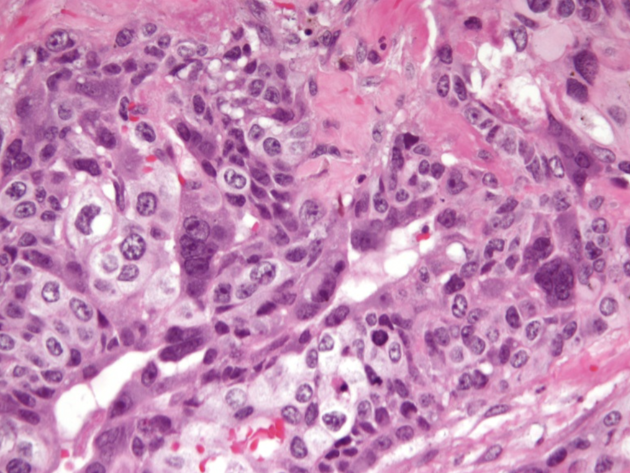

Het beeld van een choriocarcinoom zoals de patholoog dat ziet door de microscoop.